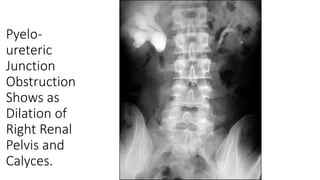

Pyelo-

ureteric

Junction

Obstruction

Shows as

Dilation of

Right Renal

Pelvis and

Calyces.